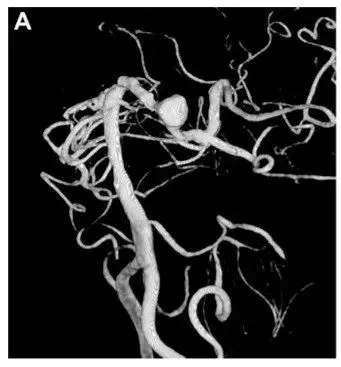

脑动静脉畸形(bAVM) 就像大脑里的不定时炸弹, 手术切除畸形团是减少出血风险并改善患者生活质量的主要方式,可手术风险有多大?要如何评估? 传统评估主要看畸形团大小、位置是否关键等。...